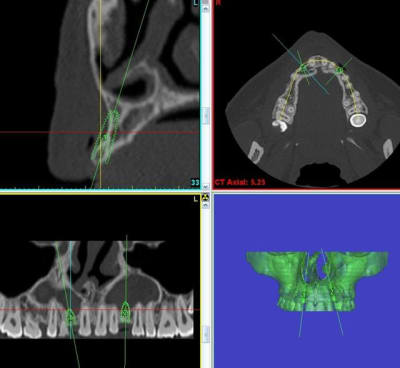

c'est pas les maigres images du scan publiées sur nonol qui te montrent l'ampleur du défaut et du défi esthétique de ce cas...

Voici le cas a venir : Agénésie de 22.

alors, on pourrais surement faire de l'expansion ( la simulation est avec un implant 3 x 12 ). Mais comme cela ressemble beaucoup a l'echec que j'ai présenté dans " erreur, ratage ", je pars pour une greffe en onlay. Avec le jeune homme et la maman, on a choisit d'éviter un deuxieme site opératoire, donc pas de prelevement buccal.

et celui là, vous le sentez comment?

précision...cette jeune femme a quand même 9 agénésies...